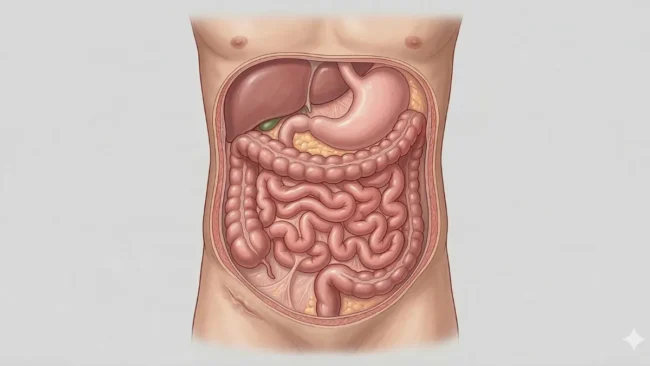

Grande parte da dificuldade médica de Bolsonaro começou com o atentado a faca sofrido em 2018. Desde aquele episódio, ele já enfrentou diversas cirurgias, desenvolvendo o chamado “abdômen hostil”. Esse é um termo utilizado para classificar uma barriga repleta de aderências, cicatrizes e fortes inflamações.

As aderências são faixas espessas de tecido cicatricial que grudam os órgãos abdominais entre si. Isso reduz consideravelmente o espaço para a passagem natural de gases e fezes. Essa condição já causou sucessivas suboclusões intestinais, exigindo dietas restritas e novas intervenções.